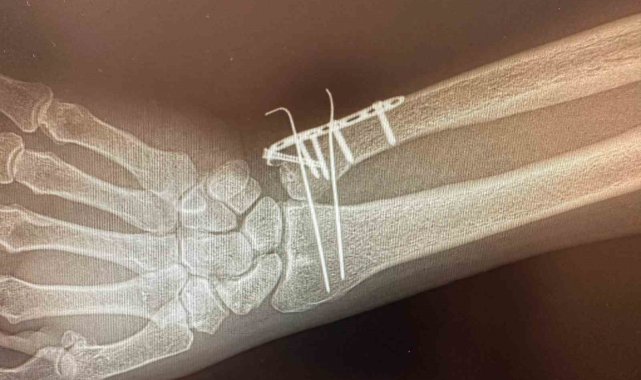

C Kollu Skopi (C-arm) cihazının tahsis edildiği Karakoçan Devlet Hastanesi'nde ortopedi ameliyatları başladı.Karakoçan Devlet Hastanesi'nde ortopedi ameliyatlarının yapılabilmesi için C Kollu Skopi (C-arm) cihazı hastaneye tahsis edildi. Hastanede göreve başlayan Ortopedi Uzmanı Halil Sami Postallı tarafından, yeni cihazın kullanımıyla birlikte kemik ameliyatlarının yapılmaya başlandığı bildirildi.C Kollu Skopinin ameliyathane ortamında hastanın iç yapısını anlık ve hareketli olarak görüntüleyen, X-ray tabanlı taşınabilir bir röntgen cihazı olduğu bildirildi. C şeklindeki yapısı sayesinde her açıdan görüntü alabilen cihazın özellikle ortopedi, travmatoloji, beyin cerrahisi, üroloji ve kardiyoloji işlemlerinde yüksek çözünürlüklü görüntü sağlayarak müdahalelerin daha güvenli ve hızlı yapılmasına imkan tanıdığını aktarıldı.Cihazın özellikle kırıkların düzeltilmesi, vida ve plak uygulamaları, kalça ve diz protez ameliyatları gibi ortopedi ve travmatoloji işlemlerinde etkin şekilde kullanılacağı ifade edildi.